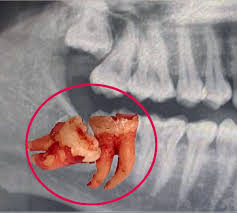

Open gum tissue to expose tooth and bone.

Remove obstructing bone for better access.

Segment and extract tooth carefully.